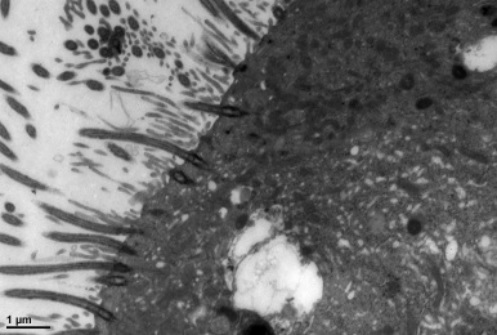

技术创新:本室独创的“石蜡电镜方法”获得北京大学新技术创新奖。该方法解决了很多疑难病理诊断问题,受到全国很多医院的关注和好评。

部分超微病理电镜图示例:

图3 石蜡电镜技术制备的标本